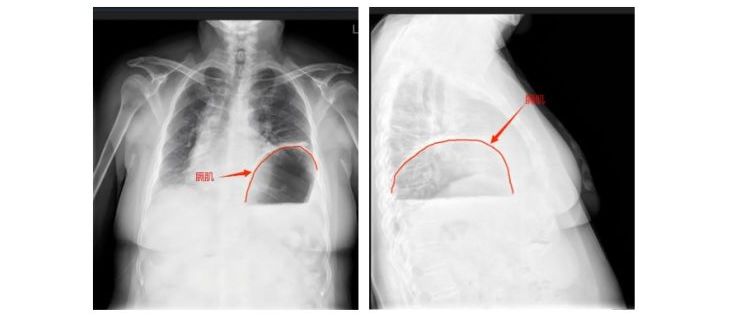

中新网黑龙江新闻7月29日电(记者 刘锡菊)近日,哈医大四院普外科二病房翟博教授收治了1例极为罕见的病例。64岁的马女士(化名)常年被打嗝、反酸烧心困扰,近几年尤为严重,且出现了严重的呼吸困难和喘憋症状。医生追问病史了解到,马女士自2000年开始出现胃胀、打嗝等情况,最严重时候连饭都吃不进去,现在出现了呼吸困难的症状,连正常活动都成了困难,严重影响了马女士的日常生活和生命安全。经多方辗转问诊,马女士找到哈医大...